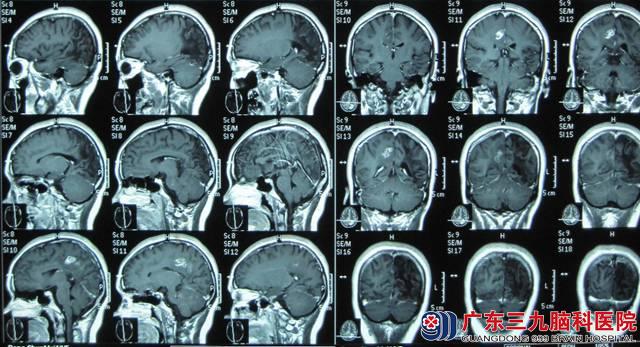

小邓,19岁,右手发作性抽搐已有15年,通过检查,CT及MRI的结果提示:右侧顶叶深部白质内病灶,血清裂头蚴抗体呈阳性。神经外六科的吴杰主任诊断为:1、症状性癫痫,2、右侧顶叶中央区脑裂头蚴病。

术前颅内影像